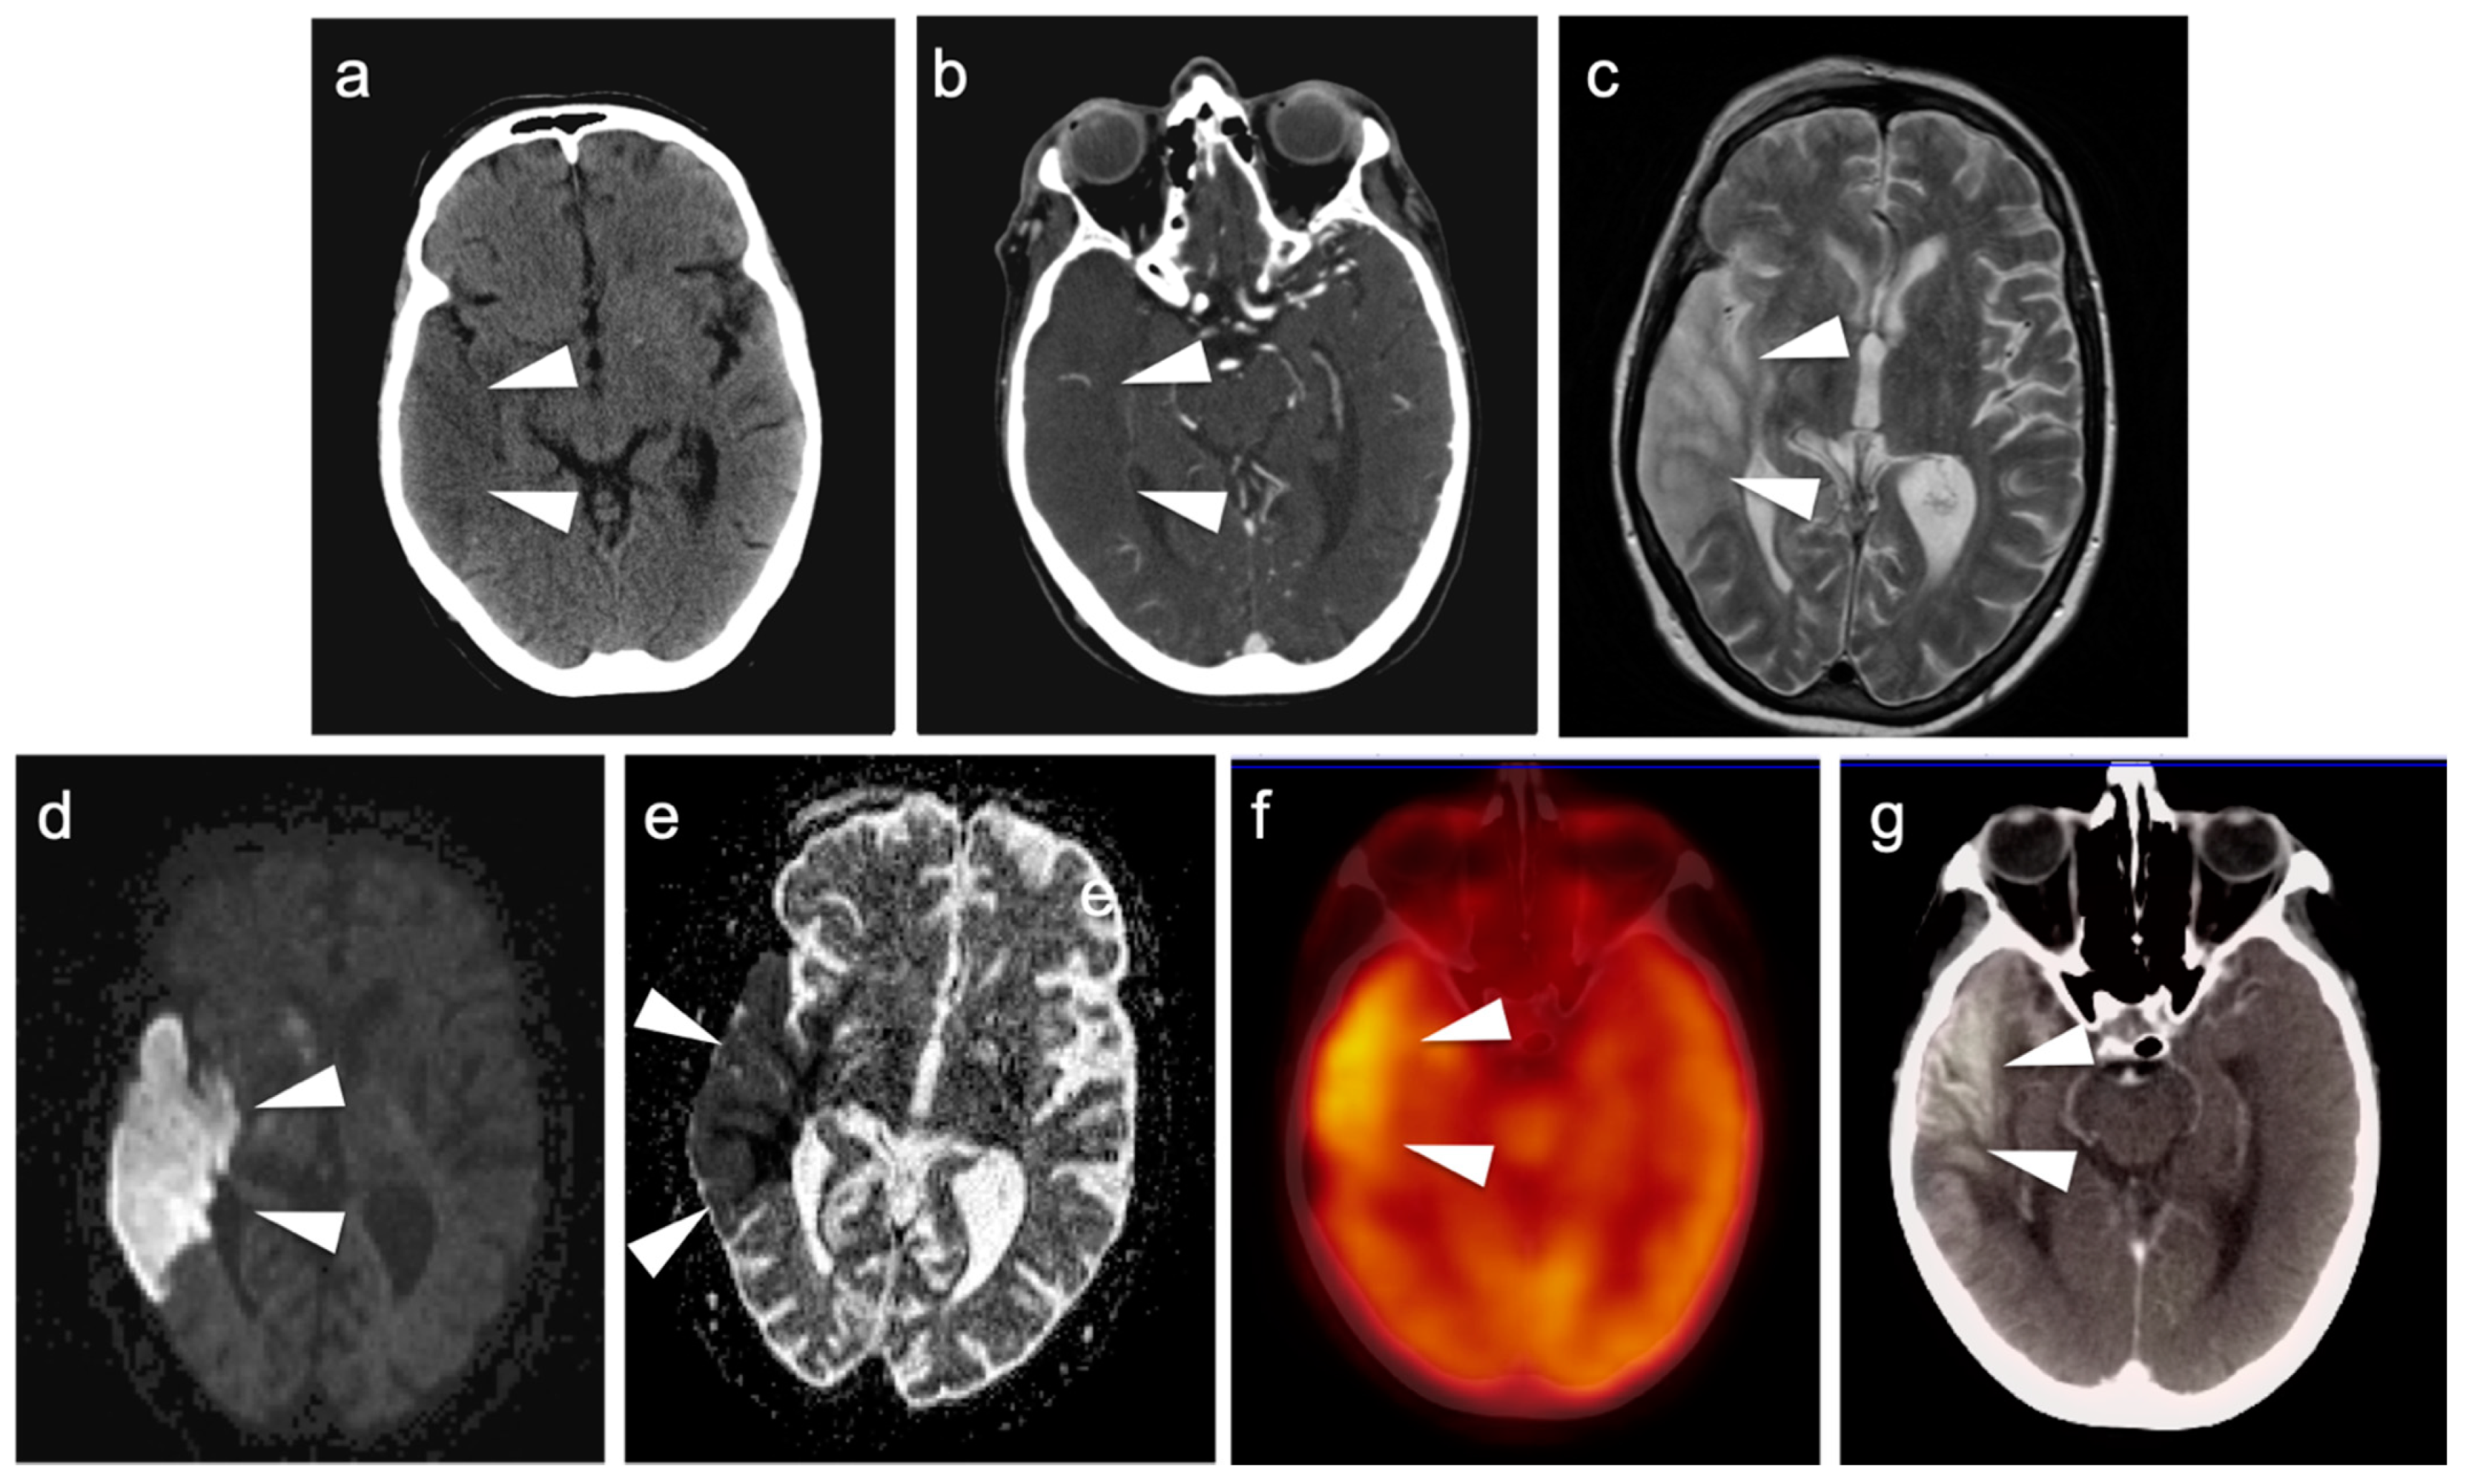

3.5. Brain Metastases

3.6. Response to Therapy

3.7. Meningioma